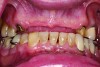

A 63-year-old African-American female presented at the University of North Carolina General Dentistry Student Clinic with a chief complaint that she was missing posterior teeth on both arches and said she would like to replace them (Figure 8).

The patient was concerned about esthetics because she was a school teacher. Her dental history revealed that she had removable partial cobalt chromium dentures that no longer fit and she had not used them for a long period. Her medical history at the initial examination revealed that she had type 2 diabetes mellitus, hypertension, and hyperlipidemia, all of which was controlled. However, she had no medical contraindication for dental care or oral surgical procedures.

The patient was presented with multiple treatment options to address her dental problems, including cast-metal partial dentures, acetal resin flexible partial dentures, and implants to replace the missing teeth and provide a first-molar occlusion. The patient initially opted for implants. During the planning phase for the implant therapy, the patient was hospitalized due to her diabetes and her physician advised against this first choice. Thus, the patient’s treatment plan was modified, and she consented to receiving acetal resin RPDs versus cast-metal RPDs due to her esthetic concerns.

A conventional RPD treatment protocol started with designing the RPDs and was followed by tooth and mouth preparation and final impressions. The RPD frameworks were fabricated using acetal resin (Myerson DuraCetalTM, www.duracetal.com) by Drake Precision Dental Laboratory in Charlotte, North Carolina (Figure 9).

Fig 8. Intraoral pre-operative photograph showing multiple missing posterior teeth in both arches.